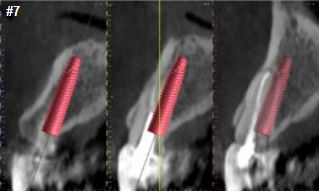

Upon prosthetic evaluation, since bothteeth were deemed unrestorable, the replacement plan an implant supported restoration. Radiographically, tooth #7 exhibited a moderate-sized periapical radiolucency.During the initial examination appointment, a CBCT and I-tero scans were obtained along with the appropriate shade to start planning an immediate non-functional tem-porary restoration. An intraoral scan was sent to the lab for digital planning of the temporary restorations.

A CBCT review showed adequate bone palatal to the socket wall, so the bone density appeared to be favorable for immediate implant placement.

Both sites were prepared into the solid palatal wall of the socket and the osteotomies were under prepared to achieve a minimum high insertion torque of at least 30N to be considered for non-functional immediately loaded temporization. 4.0x16mm implants were placed with an insertion torque above 50N at both sites. The jump gaps were grafted with cortical-cancellous allograft (Life-Net Salvin) in a dual zone fashion. The most coronal zone was packed with a moderate force to create more volume in the soft tissue compartment.